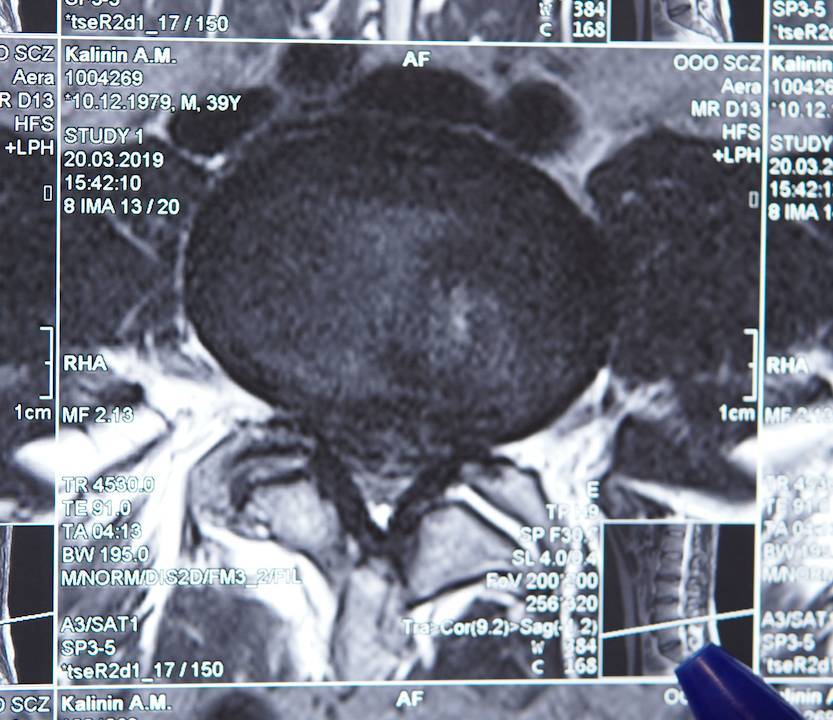

Точное определение вида патологии с помощью МРТ-исследования позволяет выбрать лучший вариант лечения и методику проведения операции. Для получения полной картины больным также назначается рентгенография и КТ.

Как выявить стеноз? Его диагностирование не доставляет проблем, заболевание легко определяется во время первичного осмотра и беседы, но результат должен быть подкреплен полным нейрохирургическим обследованием. Для получения полной картины заболевания проводится полноценный сбор анамнеза с прохождением определенных исследований:

- МРТ;

При опросе пациента нужно выяснить, какой временной промежуток наблюдаются данные изменения в организме, как долго ощущается дискомфорт при движениях, насколько серьезны симптомы. Специалист может назначить прохождение рентгенографического обследования в прямой и боковой проекции для понимания дальнейшего развития заболевания. Прохождение компьютерной томографии поможет узнать о состоянии связок и костей поясничного отдела. Прохождение МРТ покажет состояние нервной ткани.

МРТ использует мощное магнитное поле, которое, проходя через тело, попадает на сканнер и проходит компьютерную обработку. МРТ позволяет сканнировать срезы тканей, которые потом преобразуются в двух или трехмерное изображение. МРТ особенно актуально для получения информации о состоянии мягких тканей, таких как межпозвонковые диски или связки. Кроме того визуализируются спинной мозг, нервные корешки и окружающие ткани таким образом позволяя диагностировать увеличение тканей дегенерацию или опухоли.

- Магнитно-резонансная томография (МРТ).

МРТ позволяет получить доскональную и четкую картину изменений костей даже в самом начале болезни. Это дорогостоящий метод, но он выявляет любую деструкцию мягких тканей, хрящей, сосудов, нервов.